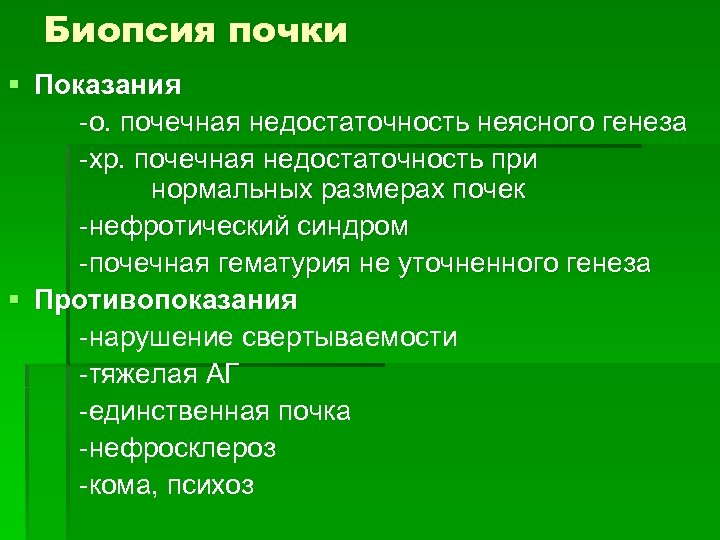

Биопсия почки § Показания -о. почечная недостаточность неясного генеза -хр. почечная недостаточность при нормальных размерах почек -нефротический синдром -почечная гематурия не уточненного генеза § Противопоказания -нарушение свертываемости -тяжелая АГ -единственная почка -нефросклероз -кома, психоз